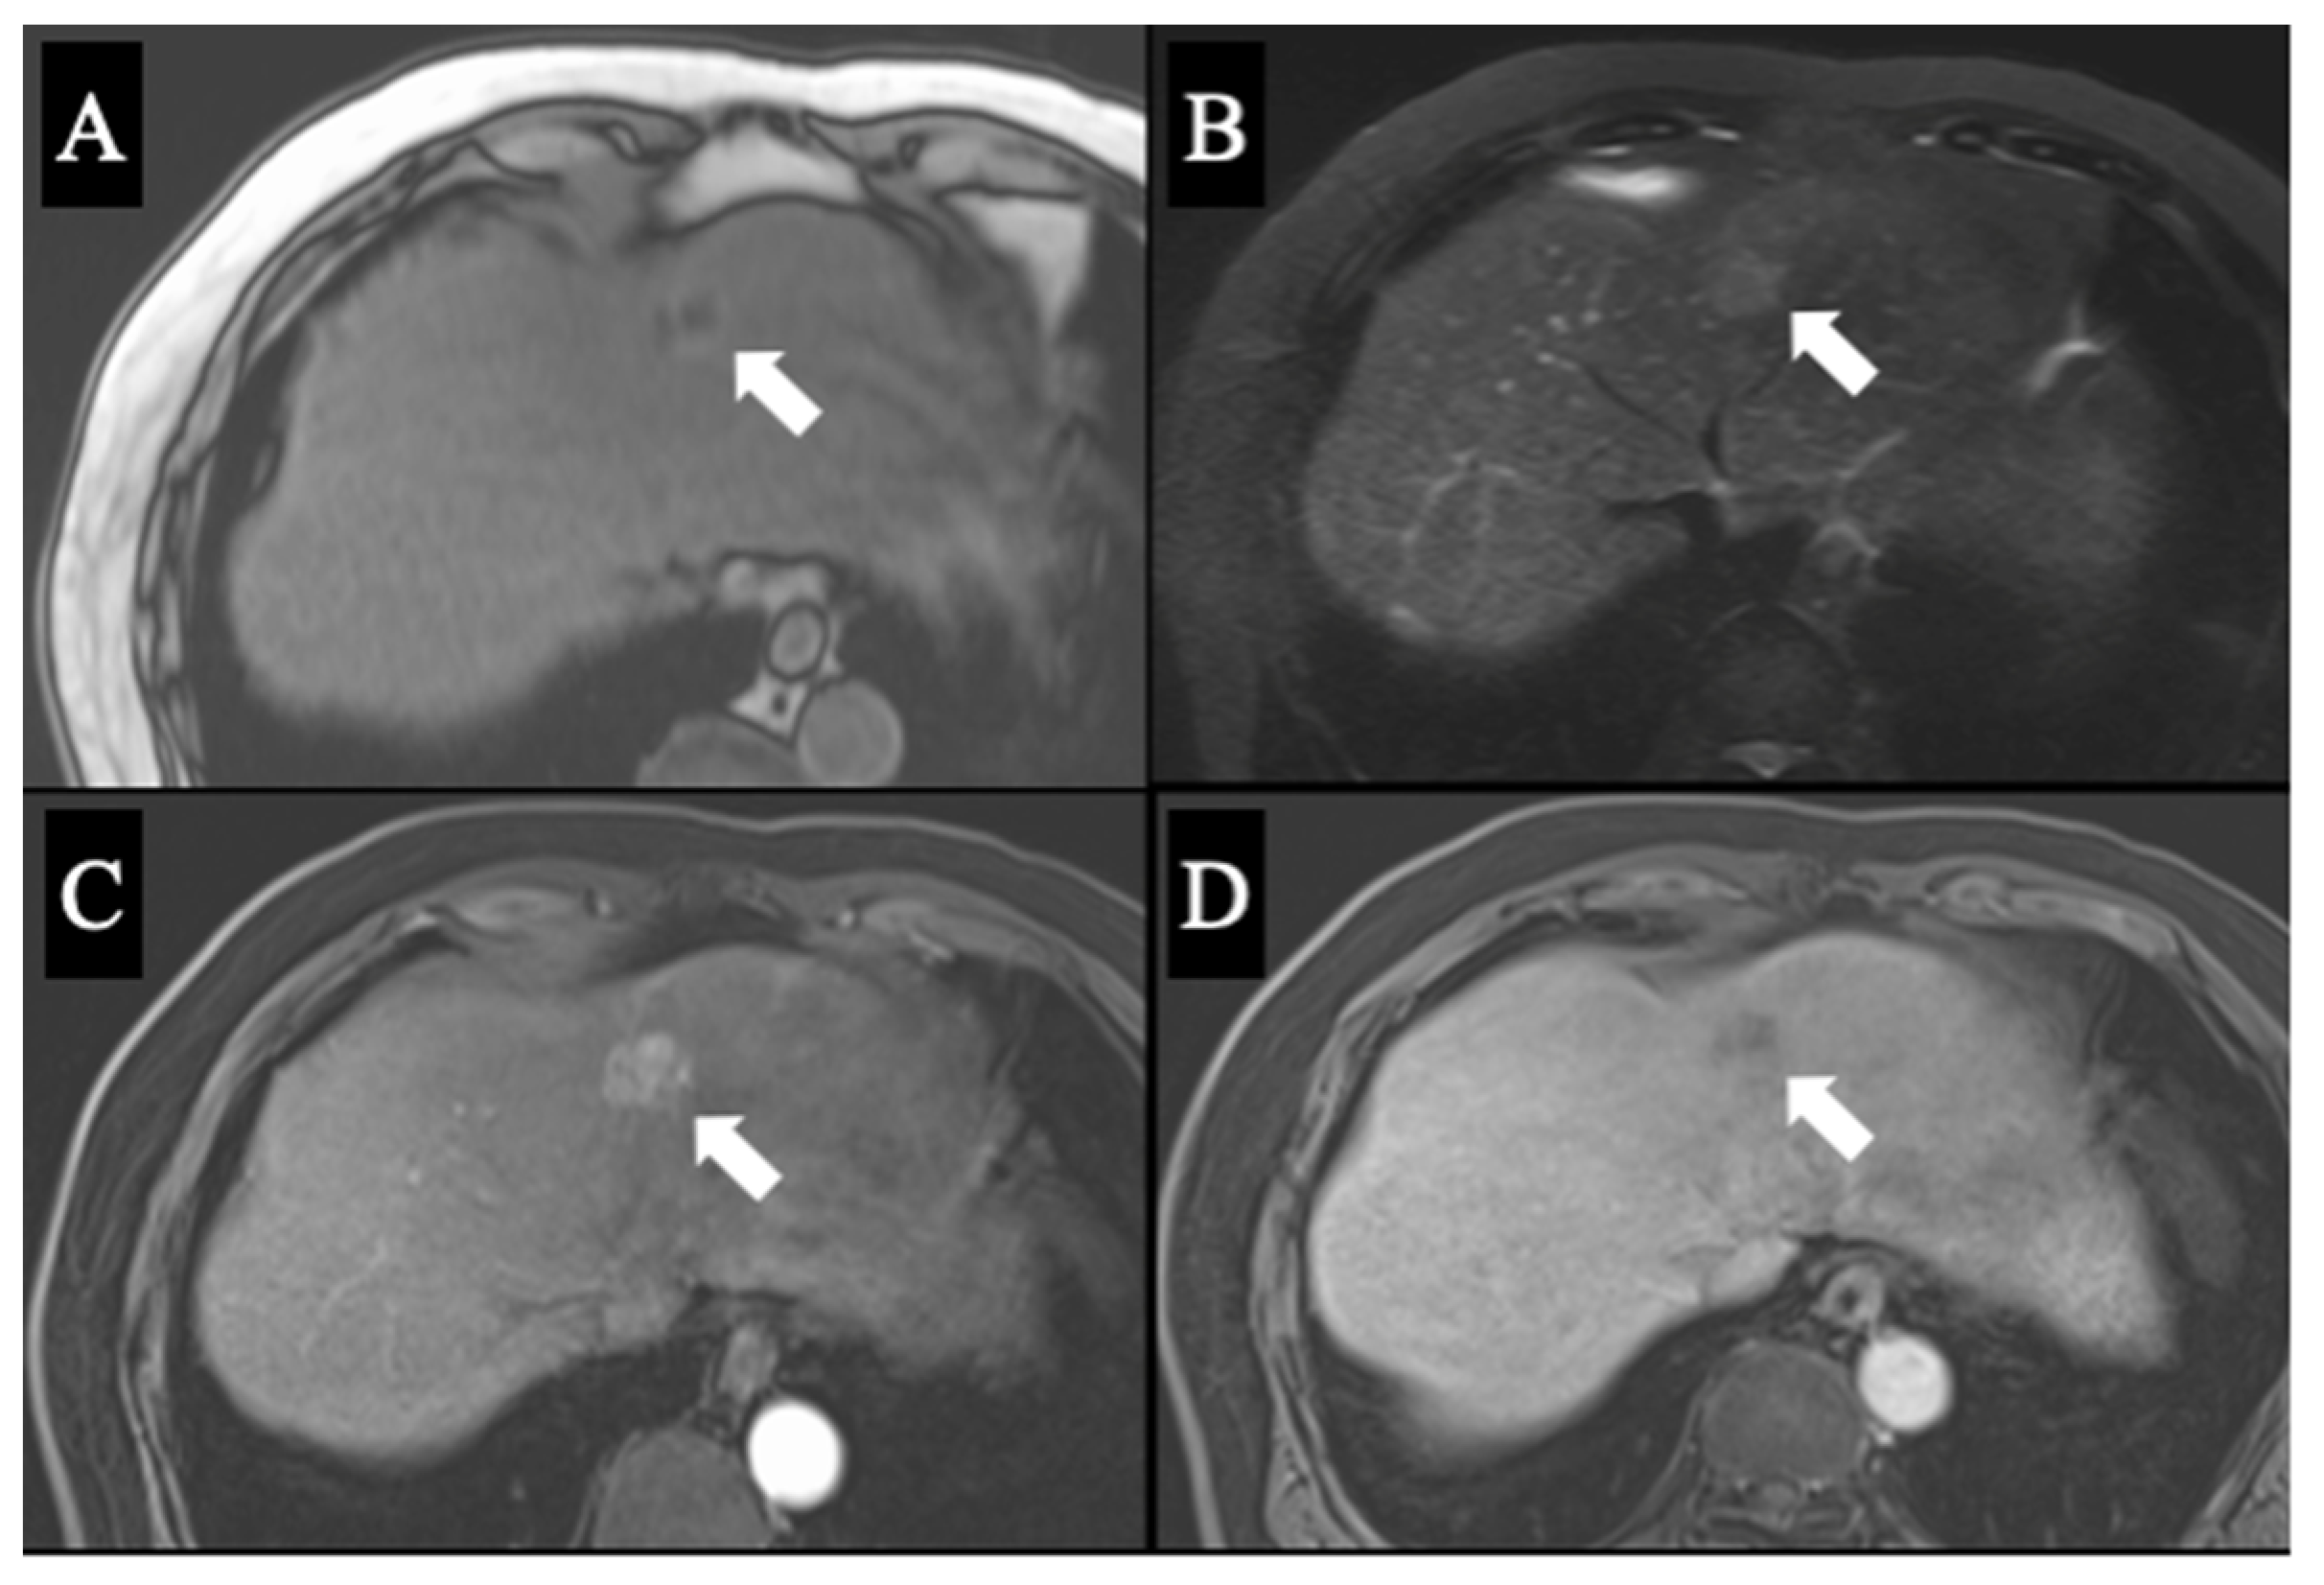

Figure 3. Magnetic resonance imaging with gadolinium ethoxybenzyl diethylenetriamine penta-acetic acid contrast agent revealed a mass which exhibited low signal intensity on T1-weighted images (A) and high signal intensity on T2-weighted (B) and diffusion-weighted images (C). Contrasted images showed a perfusion defect in the mass in the liver phase (D).

A 69-year-old man was referred for evaluation of a liver tumor detected on abdominal ultrasonography performed for nonalcoholic steatohepatitis follow-up. Blood testing showed elevations in concentrations of aspartate transaminase (56 U/L), alanine transaminase (51 U/L), and protein induced by vitamin K absence-II (224 mAU/mL). Other tumor markers and hepatitis virus markers were negative. The indocyanine green retention rate at 15 minutes was 15.2% and Child–Pugh score was 5 points (class A), suggesting good hepatic function. Computed tomography (CT) showed a 2.4 × 2.0 cm hypodense mass in the left lobe of the liver (S2/3/4b) which exhibited early arterial enhancement and washout (Figure 1). Hepatocellular carcinoma was highly suspected. In addition, the ligamentum teres was connected to the right anterior branch of the portal vein, and the gallbladder was located to its left, indicating RSLT (Figure 2). On magnetic resonance imaging, the mass was low signal intensity on T1-weighted images and high signal intensity on T2-weighted and diffusion-weighted images; contrasted imaging using gadolinium ethoxybenzyl diethylenetriamine penta-acetic acid revealed a perfusion defect in the mass in the liver phase (Figure 3). Three-dimensional CT (Synapse Vincent®︎; Fujifilm Medical, Tokyo, Japan) demonstrated right posterior, right anterior, and left branches of the portal vein. The left branch branched into P2 and P3 after two P4 branches separated. A right inferior hepatic vein and V8 were present (Figure 4). Magnetic resonance cholangiopancreatography revealed that the bile duct system was trifurcated into right posterior, right anterior branch, and left branches (Figure 5). After the pertinent anatomy was clarified and the preoperative evaluation was completed, we elected to perform laparoscopic extended lateral sectionectomy.